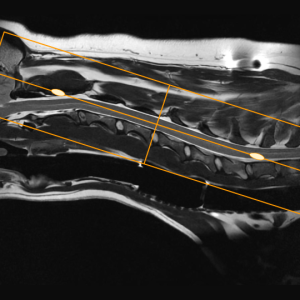

Main Gallery

Playing with a photo gallery function. It is possible to have multiple galleries, each within a namespace.